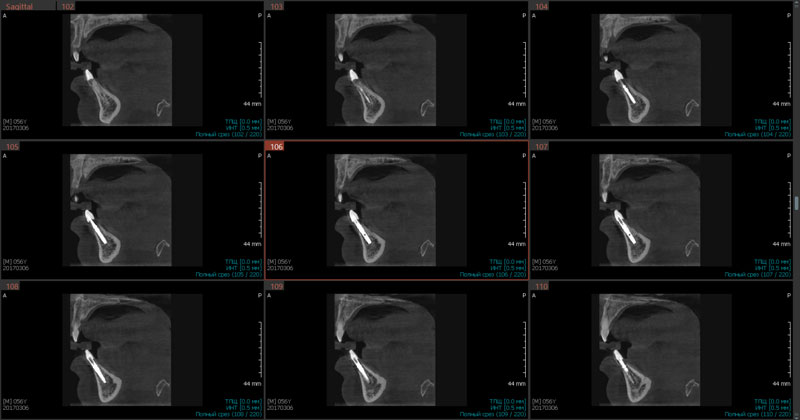

Рис.7 Кросс-секции для выявления градуса наклона имплантатов в области 31,41 зубов при первичной стабильности. Инклинация имплантатов корректна

Следует выделить кросс-секции, которые обеспечивают полную ясность при анализе, моделировании виртуального имплантата, проверке корректности его установки, выделяя важные показатели клинического случая: градус наклона, визуализация качества эндодонтического лечения соседних зубов (Рис.7).